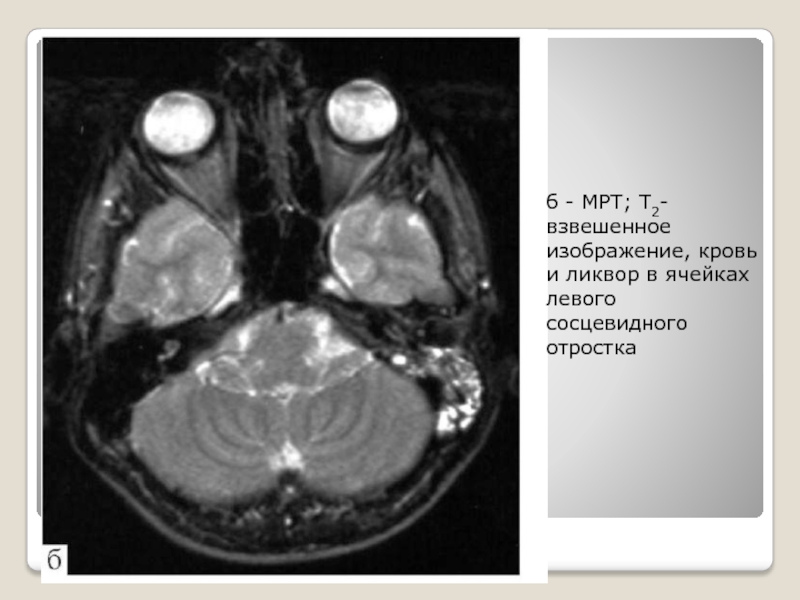

Слайд 20б - МРТ; Т2-взвешенное изображение, кровь и ликвор в ячейках

левого сосцевидного отростка

б - МРТ; Т2-взвешенное изображение, кровь и ликвор в ячейках левого сосцевидного отростка